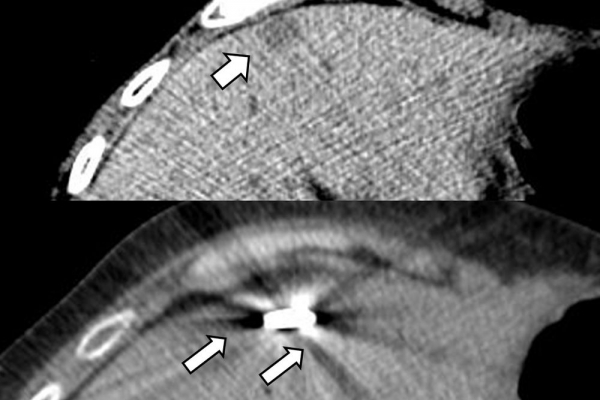

Πρόκειται για την πιο σύγχρονη τοπική θεραπεία όγκων του ήπατος, του νεφρού, του πνεύμονα, των οστών και των όγκων μαλακών μορίων. Παθοφυσιολογικά βασίζεται στην τοπική καταστροφή των καρκινικών κυττάρων με τη δημιουργία ιδιαίτερα υψηλών θερμοκρασιών εντός του όγκου. Αυτό επιτυγχάνεται με τοποθέτηση ειδικών ηλεκτροδίων εντός του όγκου υπό ακτινολογική καθοδήγηση (αξονικός τομογράφος ή υπέρηχος). Τα ηλεκτρόδια αυτά παράγουν υψηλή θερμοκρασία είτε με τη βοήθεια ραδιοσυχνοτήτων (RFablation), είτε με τη βοήθεια μικροκυμάτων (MWablation) και προκαλούν πηκτική νέκρωση των καρκινικών κυττάρων χωρίς να επηρεάζουν τα φυσιολογικά κύτταρα.Το αποτέλεσμα είναι μόνιμο.